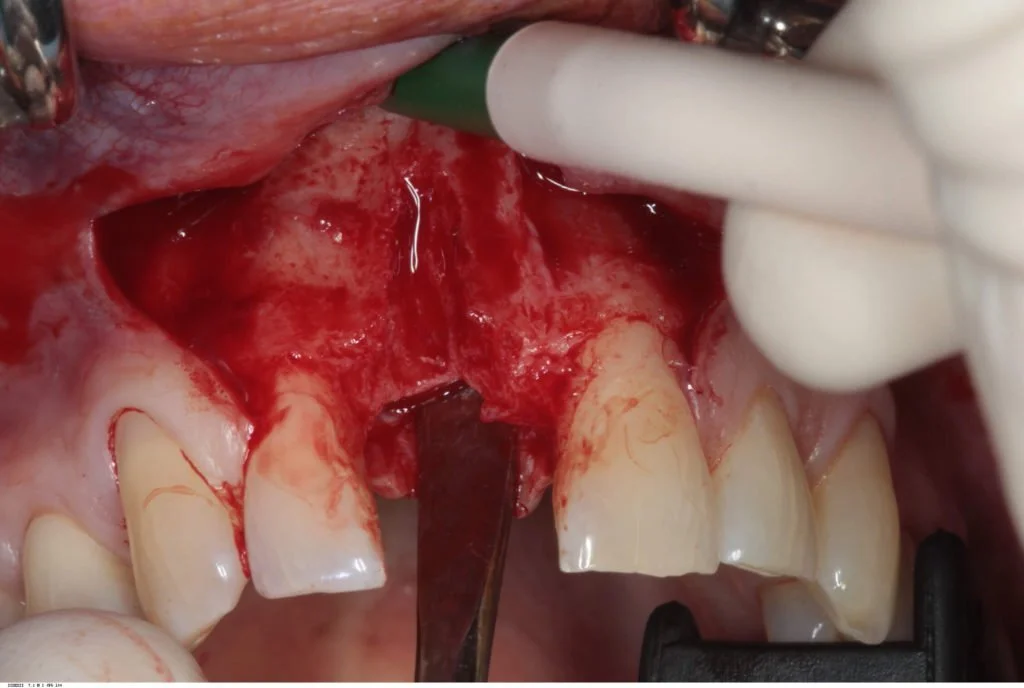

The flap was then extended slightly at the relieving incisions, and releasing incisions were made to ensure a completely tension free primary closure. Two mattress sutures (4/0 Vicryl) were used along with multiple interrupted (5/0 Vicryl) sutures.